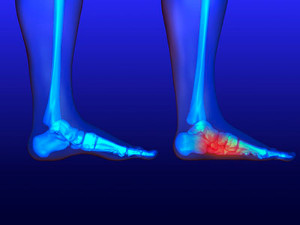

Treatments for a Broken Ankle

Ankle fractures occur when one or more of the bones that make up your ankle breaks. This can cause symptoms such as pain, bruising, tenderness, swelling, weakness, numbness, and difficulty putting weight on your ankle or walking. Ankle fractures may be treated with support devices, such as a brace or cast, that immobilize and protect the affected ankle to encourage healing. If you have a cast or brace, you may need to walk with crutches for a period of time. The pain of an ankle fracture can be relieved through over-the-counter medications that your podiatrist recommends. A broken ankle may need to be treated surgically if the fracture is severe. If you have broken your ankle, it is suggested that you seek the care of a podiatrist.

Broken Ankles

A broken ankle is experienced when a person fractures their tibia or fibula in the lower leg and ankle area. Both of these bones are attached at the bottom of the leg and combine to form what we know to be our ankle.

When a physician is referring to a break of the ankle, he or she is usually referring to a break in the area where the tibia and fibula are joined to create our ankle joint. Ankles are more prone to fractures because the ankle is an area that suffers a lot of pressure and stress. There are some obvious signs when a person experiences a fractured ankle, and the following symptoms may be present.

All About Broken Ankles

Broken ankles are a serious injury that can lead to an inability to walk, function, and also cause a significant amount of pain. A broken ankle is a break in one of the three bones in your body that connect at the ankle joint: the tibia, the fibula, and the talus. The tibia and fibula are your two primary leg bones that connect at the knee, which sit directly upon the talus bone. This is protected by a fibrous membrane that allows for movement in the ankle joint. A broken ankle is usually caused by the foot rolling under or twisting too far, causing one of these three bones to snap.

A broken ankle is different from an ankle sprain, which occurs when the ankle ligaments are ripped or torn but no bones have been broken. A sprain can still be very severe, causing bruising in the foot and an inability to hold your own weight, much like a broken ankle would. If you’re unable to stand, and suspect that you have a broken ankle, the first thing to do would be to get an immediate X-ray to determine the severity of the break.

A common cause of broken ankles is when the ankle is rolled over with enough pressure to break the bones. This usually happens during exercise, sports, or other physical activity. Another common cause is a fall or jump from a tall height.

One immediate treatment for pain relief is elevating the foot above your head to reduce blood flow to the injured area. You can also apply ice packs to your ankle to help reduce swelling, redness, inflammation, and pain. After these initial steps, getting a cast and staying off your feet as much as possible will aid in the recovery of the broken ankle. The less movement and stress the ankle has to endure, the more complete it will heal. A doctor can determine if surgery is needed in order to heal correctly. In these cases, an operation may be the only option to ensure the ability to walk properly again, followed by physical therapy and rehabilitation.

It is highly important to determine if surgery is needed early on, because a broken ankle can become much more severe than you realize. If not professionally treated, the broken ankle will inhibit your walking, daily functioning, and produce a large amount of pain. Treating your broken ankle early on will help prevent further damage to it.